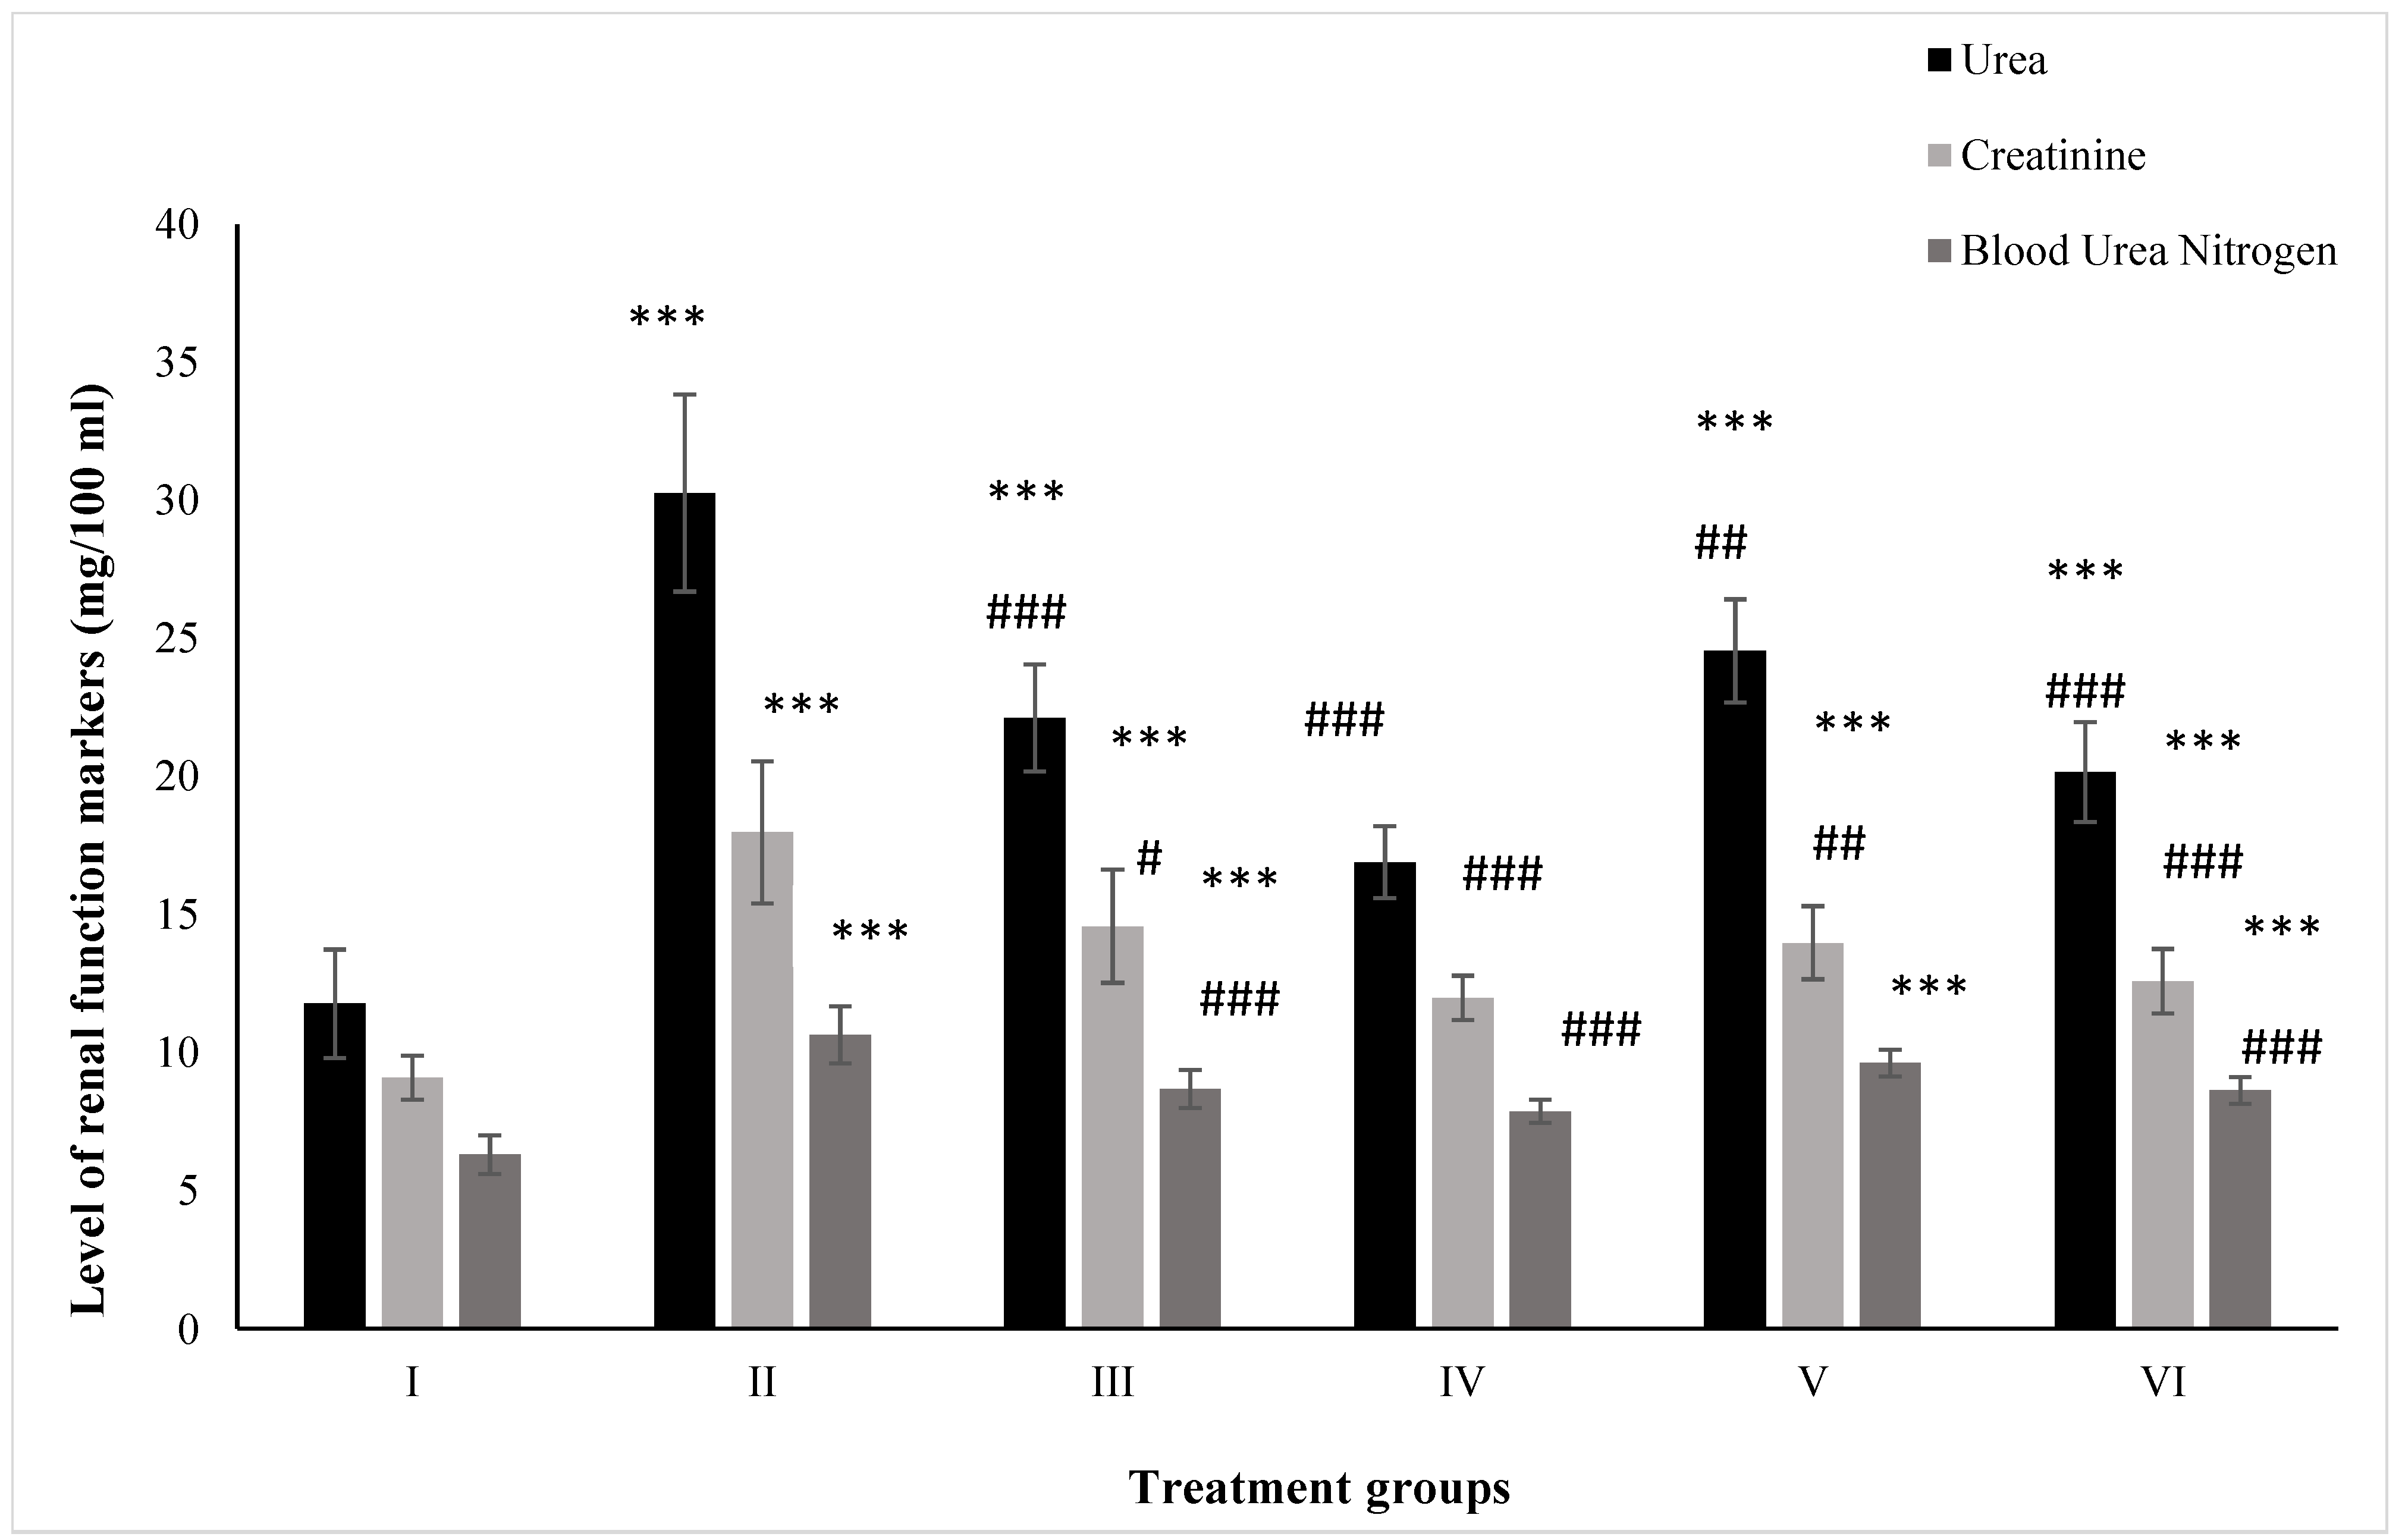

2.1. Effect on Kidney Function Markers

2.1.1. Urea

2.1.2. Creatinine

2.1.3. BUN